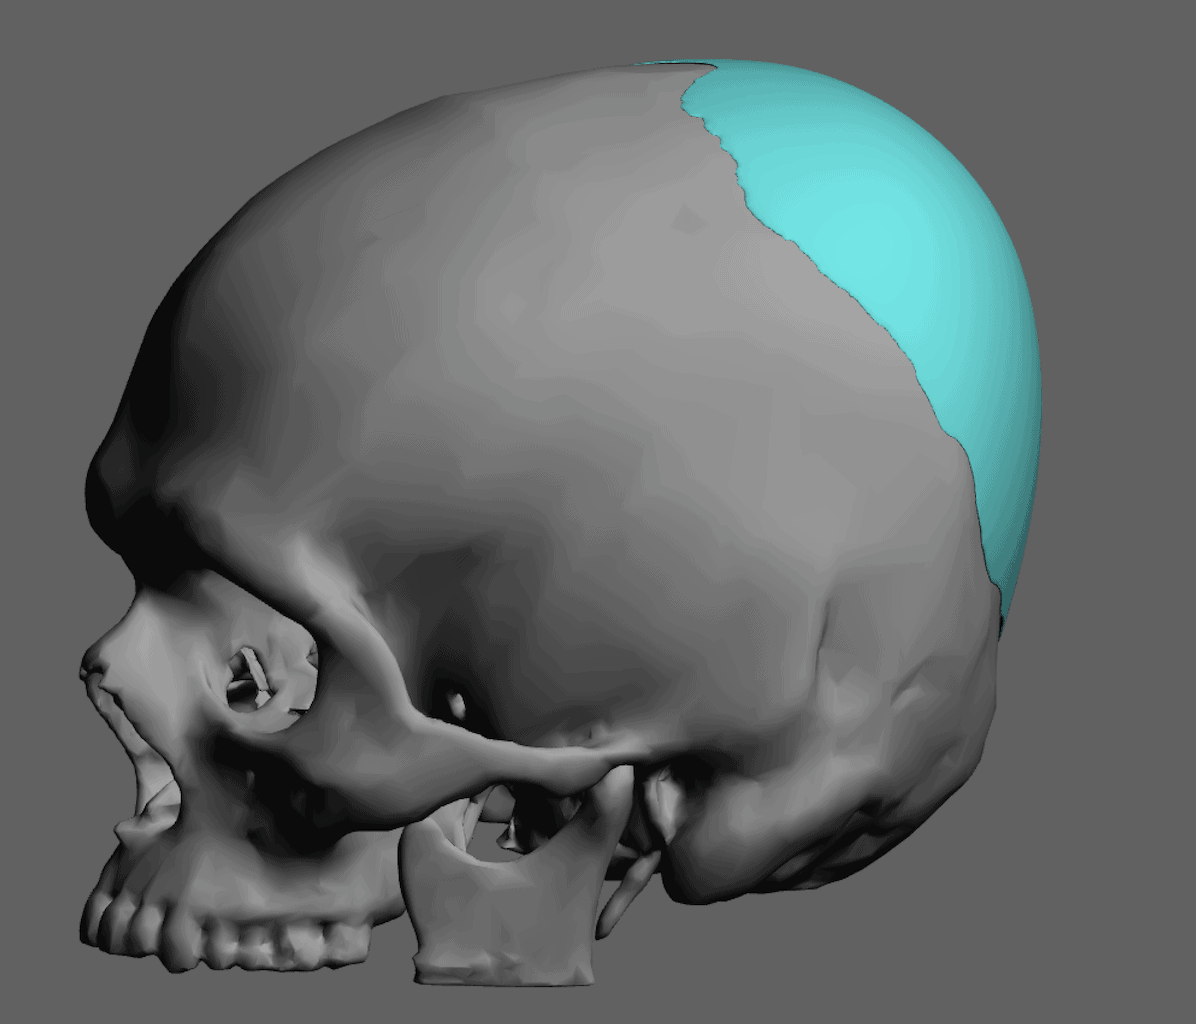

Placement of custom extended forehead-temporal implants through incisions in the crease behind the ear. (he had a prior back of head skull implant which is green in the implant designs and which the head widening implants partially covered it)

Desire for change of head shape from front view form an inverted V shape to a rounder and wider head shape.

Placement of custom extended forehead-temporal implants through incisions in the crease behind the ear. (he had a prior back of head skull implant which is green in the implant designs and which the head widening implants partially covered it)